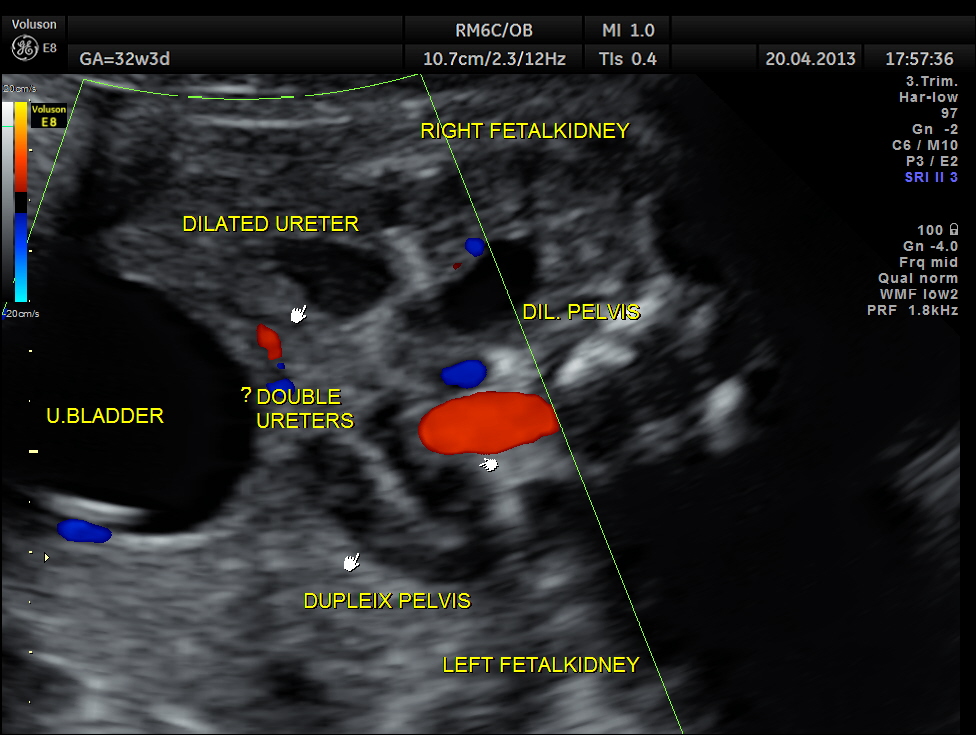

The following images show bilateral renal pelvi ectasis and bilateral dilated ureters with all the changes more in the left kidney .

The left kidney also showed possible duple-ix pelvis with double ureters arising from them . But this finding could not be confirmed in all the views .